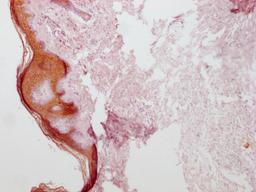

IHC image of CSB-MA555839 diluted at 1:100 and staining in paraffin-embedded human skin tissue performed on a Leica BondTM system. After dewaxing and hydration, antigen retrieval was mediated by high pressure in a citrate buffer (pH 6.0). Section was blocked with 10% normal goat serum 30min at RT. Then primary antibody (1% BSA) was incubated at 4°C overnight. The primary is detected by a Goat anti-mouse IgG polymer labeled by HRP and visualized using 0.05% DAB.